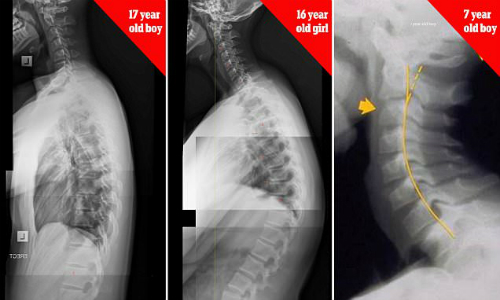

Nhiều phụ huynh khi thấy con em dùng điện thoại chỉ quan tâm liệu trẻ có xem các nội dung không phù hợp mà không nhắc nhở về tư thế ngồi. Chuyên gia trị liệu cột sống là tiến sĩ James Carter (Australia) cảnh báo trẻ em 7 tuổi có thể bị gù lưng, cong vẹo cột sống do sử dụng smartphone và tablet quá nhiều. Hội chứng được gọi là "chiếc cổ nhắn tin" đang gia tăng một cách đáng báo động.

Theo Telegraph, tiến sĩ Carter thường xuyên tiếp những bệnh nhân phàn nàn bị đau đầu mà nguyên nhân do những thiết bị điện tử. "Cách đây 2 năm, tôi đã nhận thấy có quá nhiều trường hợp như vậy, đặc biệt trẻ em và thiếu niên chiếm đến 50% số bệnh nhân", tiến sĩ cho hay. "Hiện tượng này được gọi là 'chiếc cổ nhắn tin' bởi nó xảy ra khi con người ngồi cúi đầu, dán mắt vào điện thoại liên tục hàng giờ. Từ đó dẫn đến thoái hóa đốt sống cổ; đau đầu, cổ, vai và lưng". Ngoài tổn thương cột sống, nghiện smartphone còn dẫn đến lo âu và trầm cảm.

Sammy Margo từ Hiệp hội Vật lý trị liệu Anh đồng ý với nhận định càng ngày càng có nhiều người bị tình trạng "chiếc cổ nhắn tin". "Khi cúi đầu quá lâu, bạn sẽ thay đổi toàn bộ cấu trúc xương. Kết hợp với lối sống ít vận động, điều này sẽ gây ra những hậu quả nghiêm trọng", bà nói.